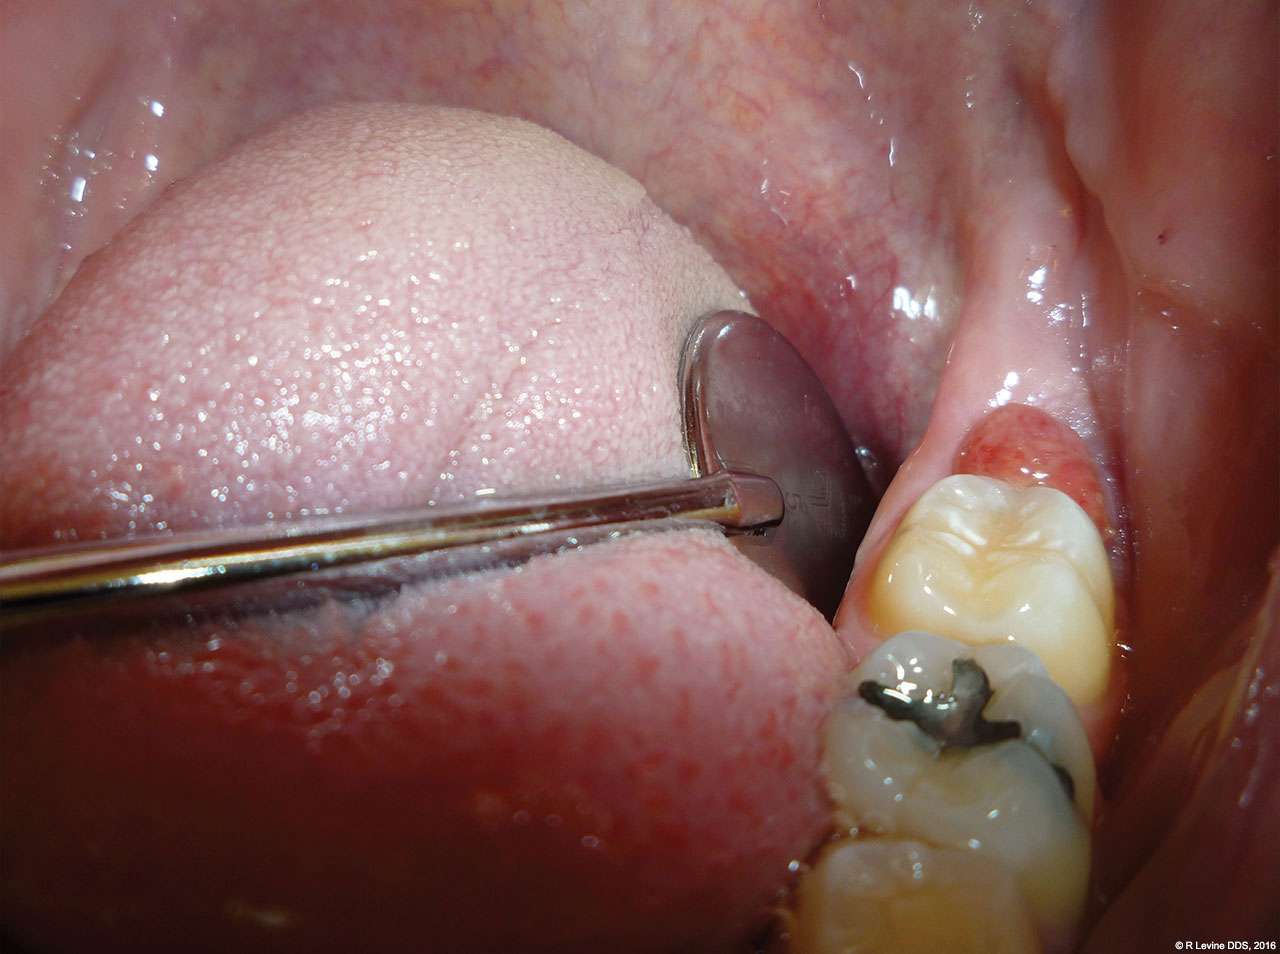

For sulcus decontamination, the laser was set to 2 W in the SuperPulse mode with repeat pulsing at a 15 millisecond pulse-width and 20 Hz repetition rate. The tip-retainer dental handpiece was used with the periodontal tip’s distal end approximately 1 mm from the base of the pocket and parallel to the surface of the tooth; an air purge was constantly supplied through the tip and was set to the highest flow.

- After the removal of lesion, a periodontal tip was placed approximately 1 mm from the base of the pocket to decontaminate the sulcus area. Laser energy was administered using horizontal movements along the entire distal sulcular aspect.